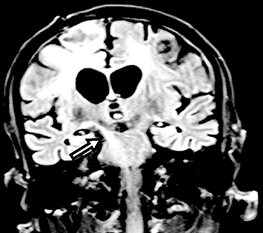

Experience of selective intra-arterial chemotherapy for Retinoblastoma

Hussain Ahmad Khaqan , et al